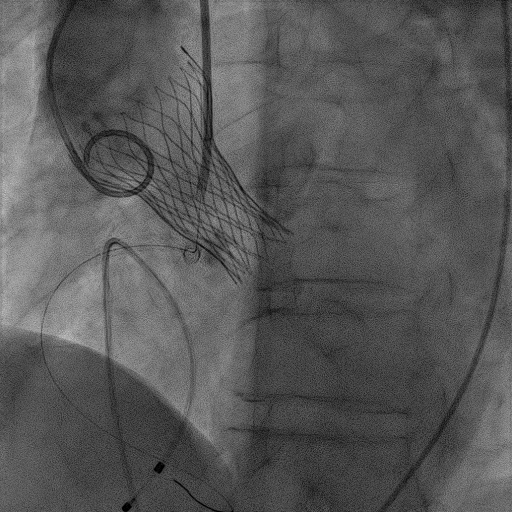

手术过程:

患者麻醉方式采取监护麻醉,建立静脉通路后,穿刺右侧股动脉预置两把Proglide缝合器,置入鞘管,穿刺右侧股静脉,置入鞘管,临时起搏器经股静脉置入心室。经右股动脉行冠脉造影提示冠脉无明显狭窄。加硬导丝送至左心室内,22mm球囊预扩张,VitaFlow 27瓣膜精准定位并释放,瓣膜形态良好,结果满意。应用ProGlide缝合右股动脉穿刺部位并拔除临时起搏电极。术后患者即刻苏醒,安全返回普通病房。

主动脉根部造影

22mm球囊预扩张

VitaFlow 27瓣膜精准定位

瓣膜形态良好,结果满意